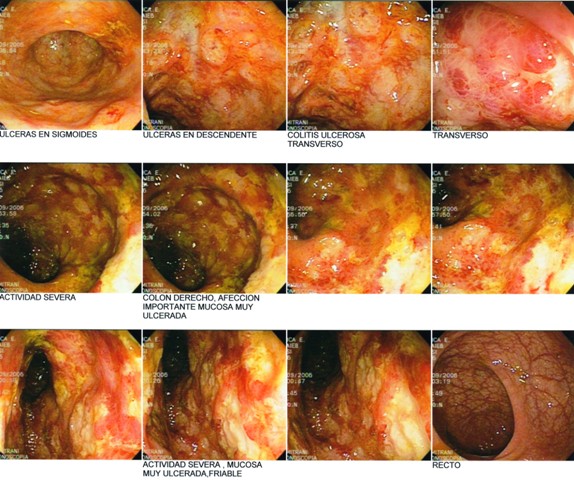

This is how a Crohn’s disease looks in colonoscopy.

Great pics! This is an effective way of how to explain this condition to patients.